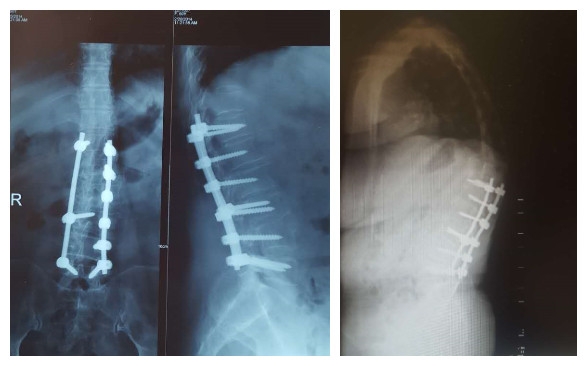

图7 术前-术后1个月-术后1个月外观